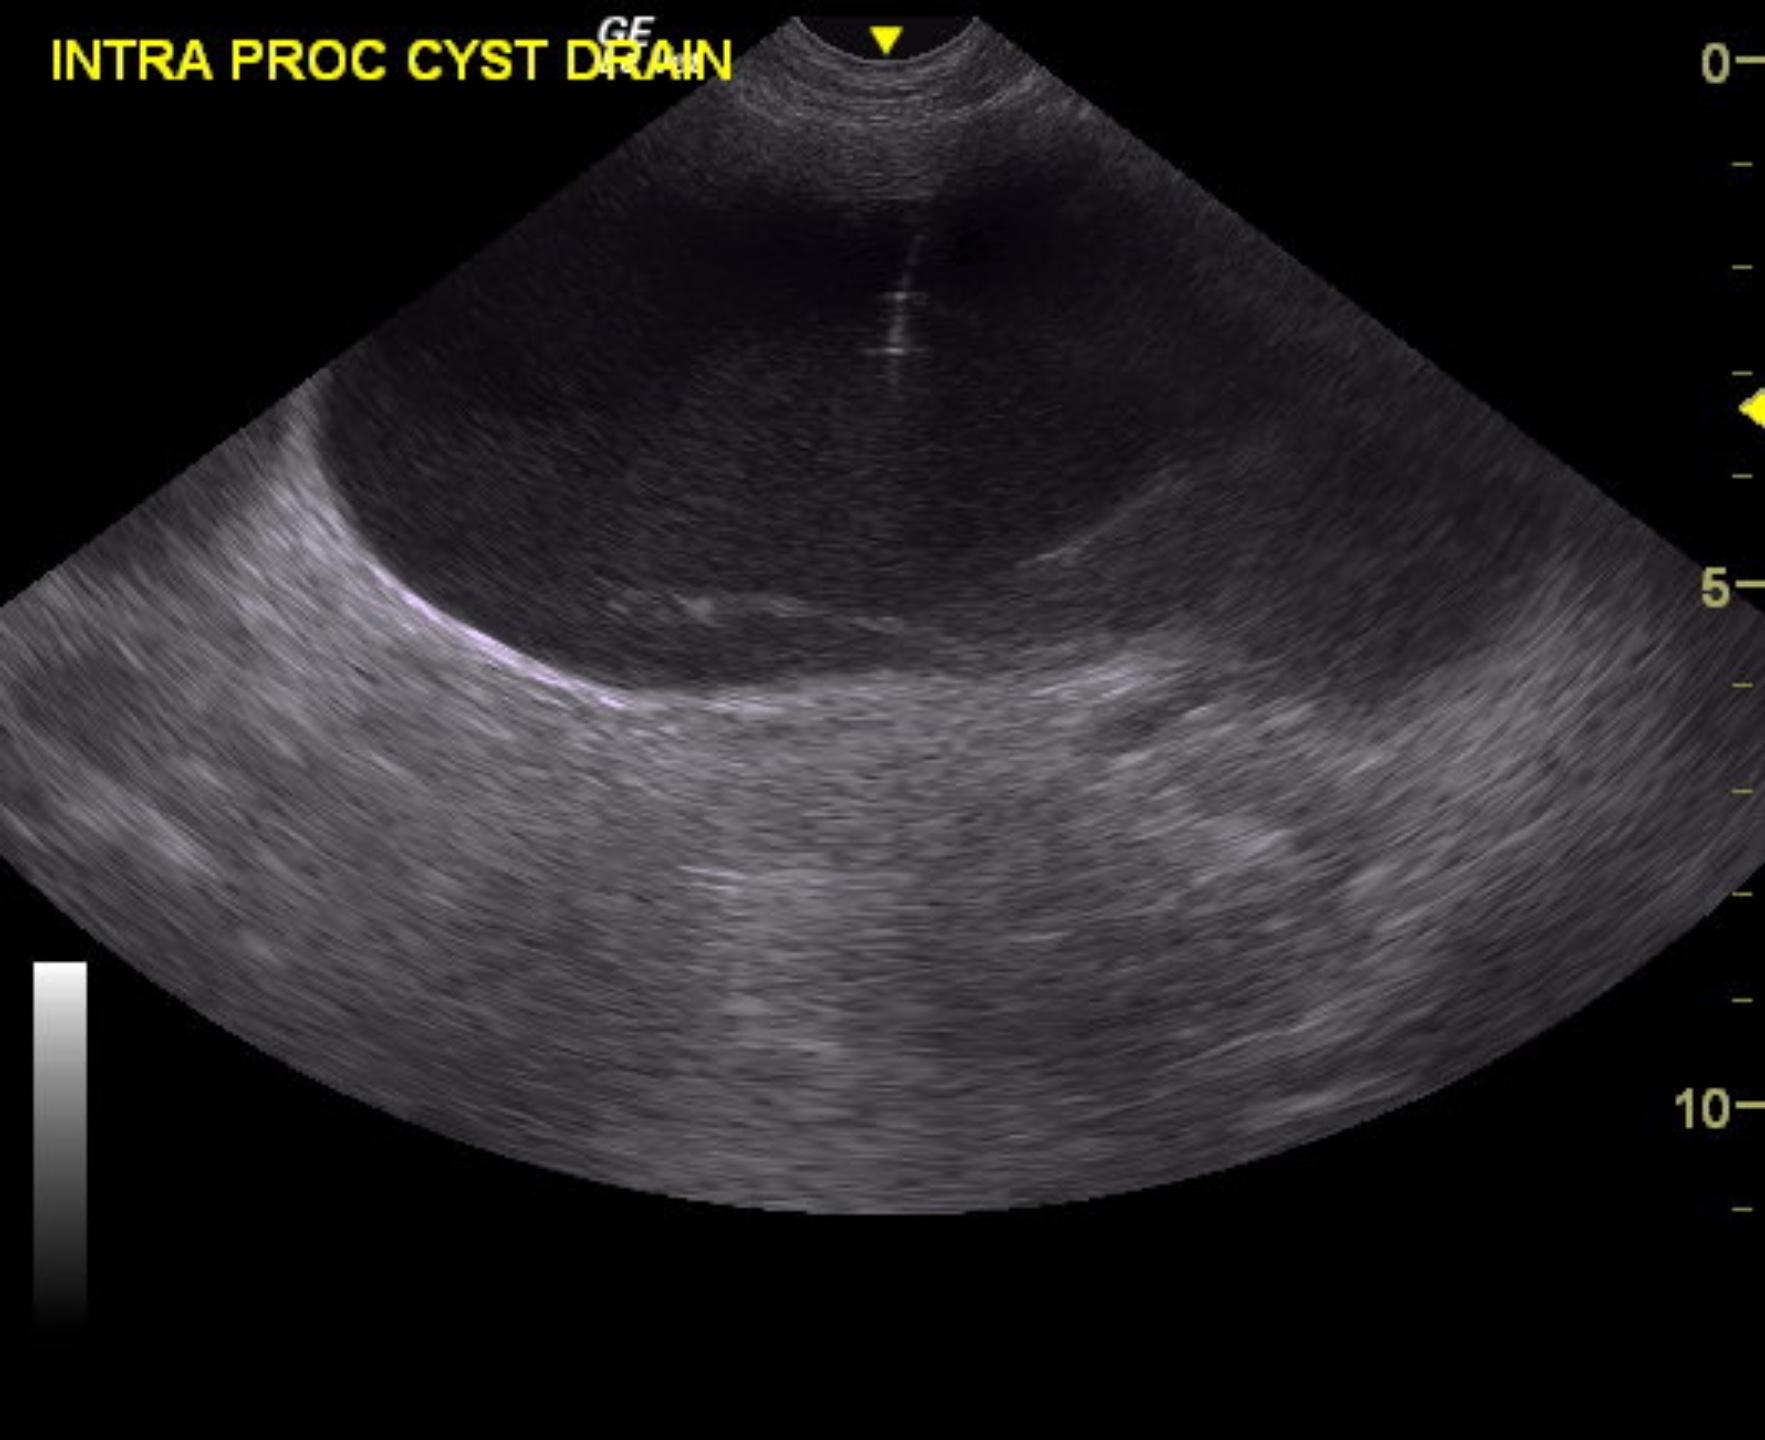

A 7-year-old intact male Boxer was presented for evaluation of tenesmus and hematochezia with normal urinalysis, CBC, and serum biochemistry. Prostatomegaly was present on rectal palpation. Survey radiographs showed a mass caudal to the urinary bladder.